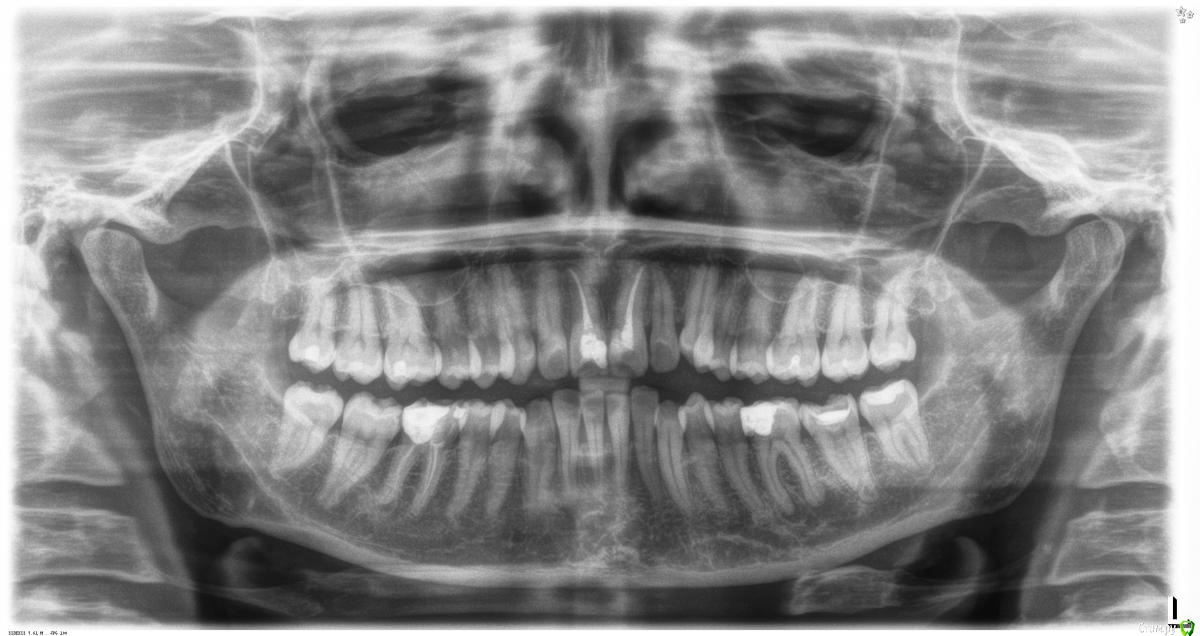

St. Опубликовано 30 января, 2018 Поделиться Опубликовано 30 января, 2018 Хочу поделится не совсем стандартным случаем и попросить совета.Итак, 36 зуб привел пациентку к нам поздним вечером с острой болью при накусывании и самопроизвольной дергающей пульсирующей болью от которой она не спала ночь накануне. Делаем снимок - периодонтит, обсудили все риски и вариант удаления, пациент выбрал лечение. Зуб неподвижен, парадонтильных карманов нет, тканей своих много, перкуссия ++, пальпация в обл корней +, переходная складка спокойная. Открыли, каналы ни разу не пустые, как можно было решить по диагностическому снимку, заполнены неконтрастной РФП. Распломбировали, получили немного экссудата, кальций, времянка. Через 2 дня встретились повторно перестраховаться т.к. пац планировал поездку, еще раз то же самое, опять кальций на 14 дней. В этот визит стало намного легче.Через 14 дней все ок, ничего не болит, в каналах при открытии немного экссудата, но в процессе мед.обработки все высушилось. Гипохлорит, эдта, перекись, хлоргексидин 2%. Медиальные 35.04, дистальные 40.04 и 45.02. Времянка композит. Постпломбировочные боли несколько дней, потом все прошло.Через 3 недели пац обращается повторно с теми же жалобами. Перкуссия 37 и 36 ++ , пальпация ++ между 36 и 37, переходная складка норма, подвижности нет, времянка на месте.Отправили на КТ. Очаг само собой большой, в одном месте граничит с нижнечелюстным каналом, с периодонтом 37 не связан. Кортикалка нижней челюсти очень плотная и толстая. С пломбировкой каналов все хорошо.Распломбировала дистальные ( прямее, шире и больше сообщаются с процессом).Долго мыли, получила гнойносерозный экссудат сначала вытекающий самотеком. Кальций. Пазначила аугментин и нимесил. Через сутки легче, перкуссия еще ++, пульсирующих болей нет, экссудата все равно много.Через 4 дня симптоматики нет, перкуссия и пальпация отрицательна, экссудат серозный , но много, канал не высушить. Опять кальций.Решила оставить на 10 дней.1. Брались ли бы Вы изначально за этот случай и как бы вели?2. Как убрать экссудативный компонент и почему так долго продолжается? Ссылка на комментарий